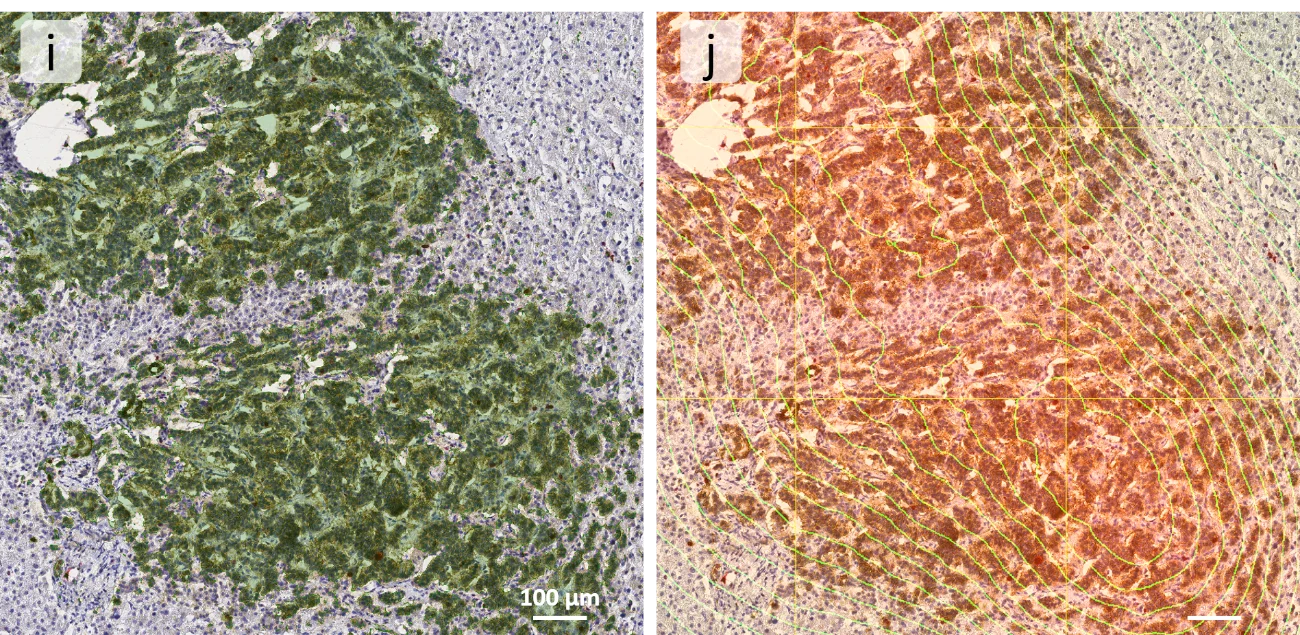

Following the cell segmentation and marker detection, the whole NCAM positive cell area (i) was detected, highlighted by a green mask, and further, a density mask (j) was applied to find NCAM high-density spots in the sample.